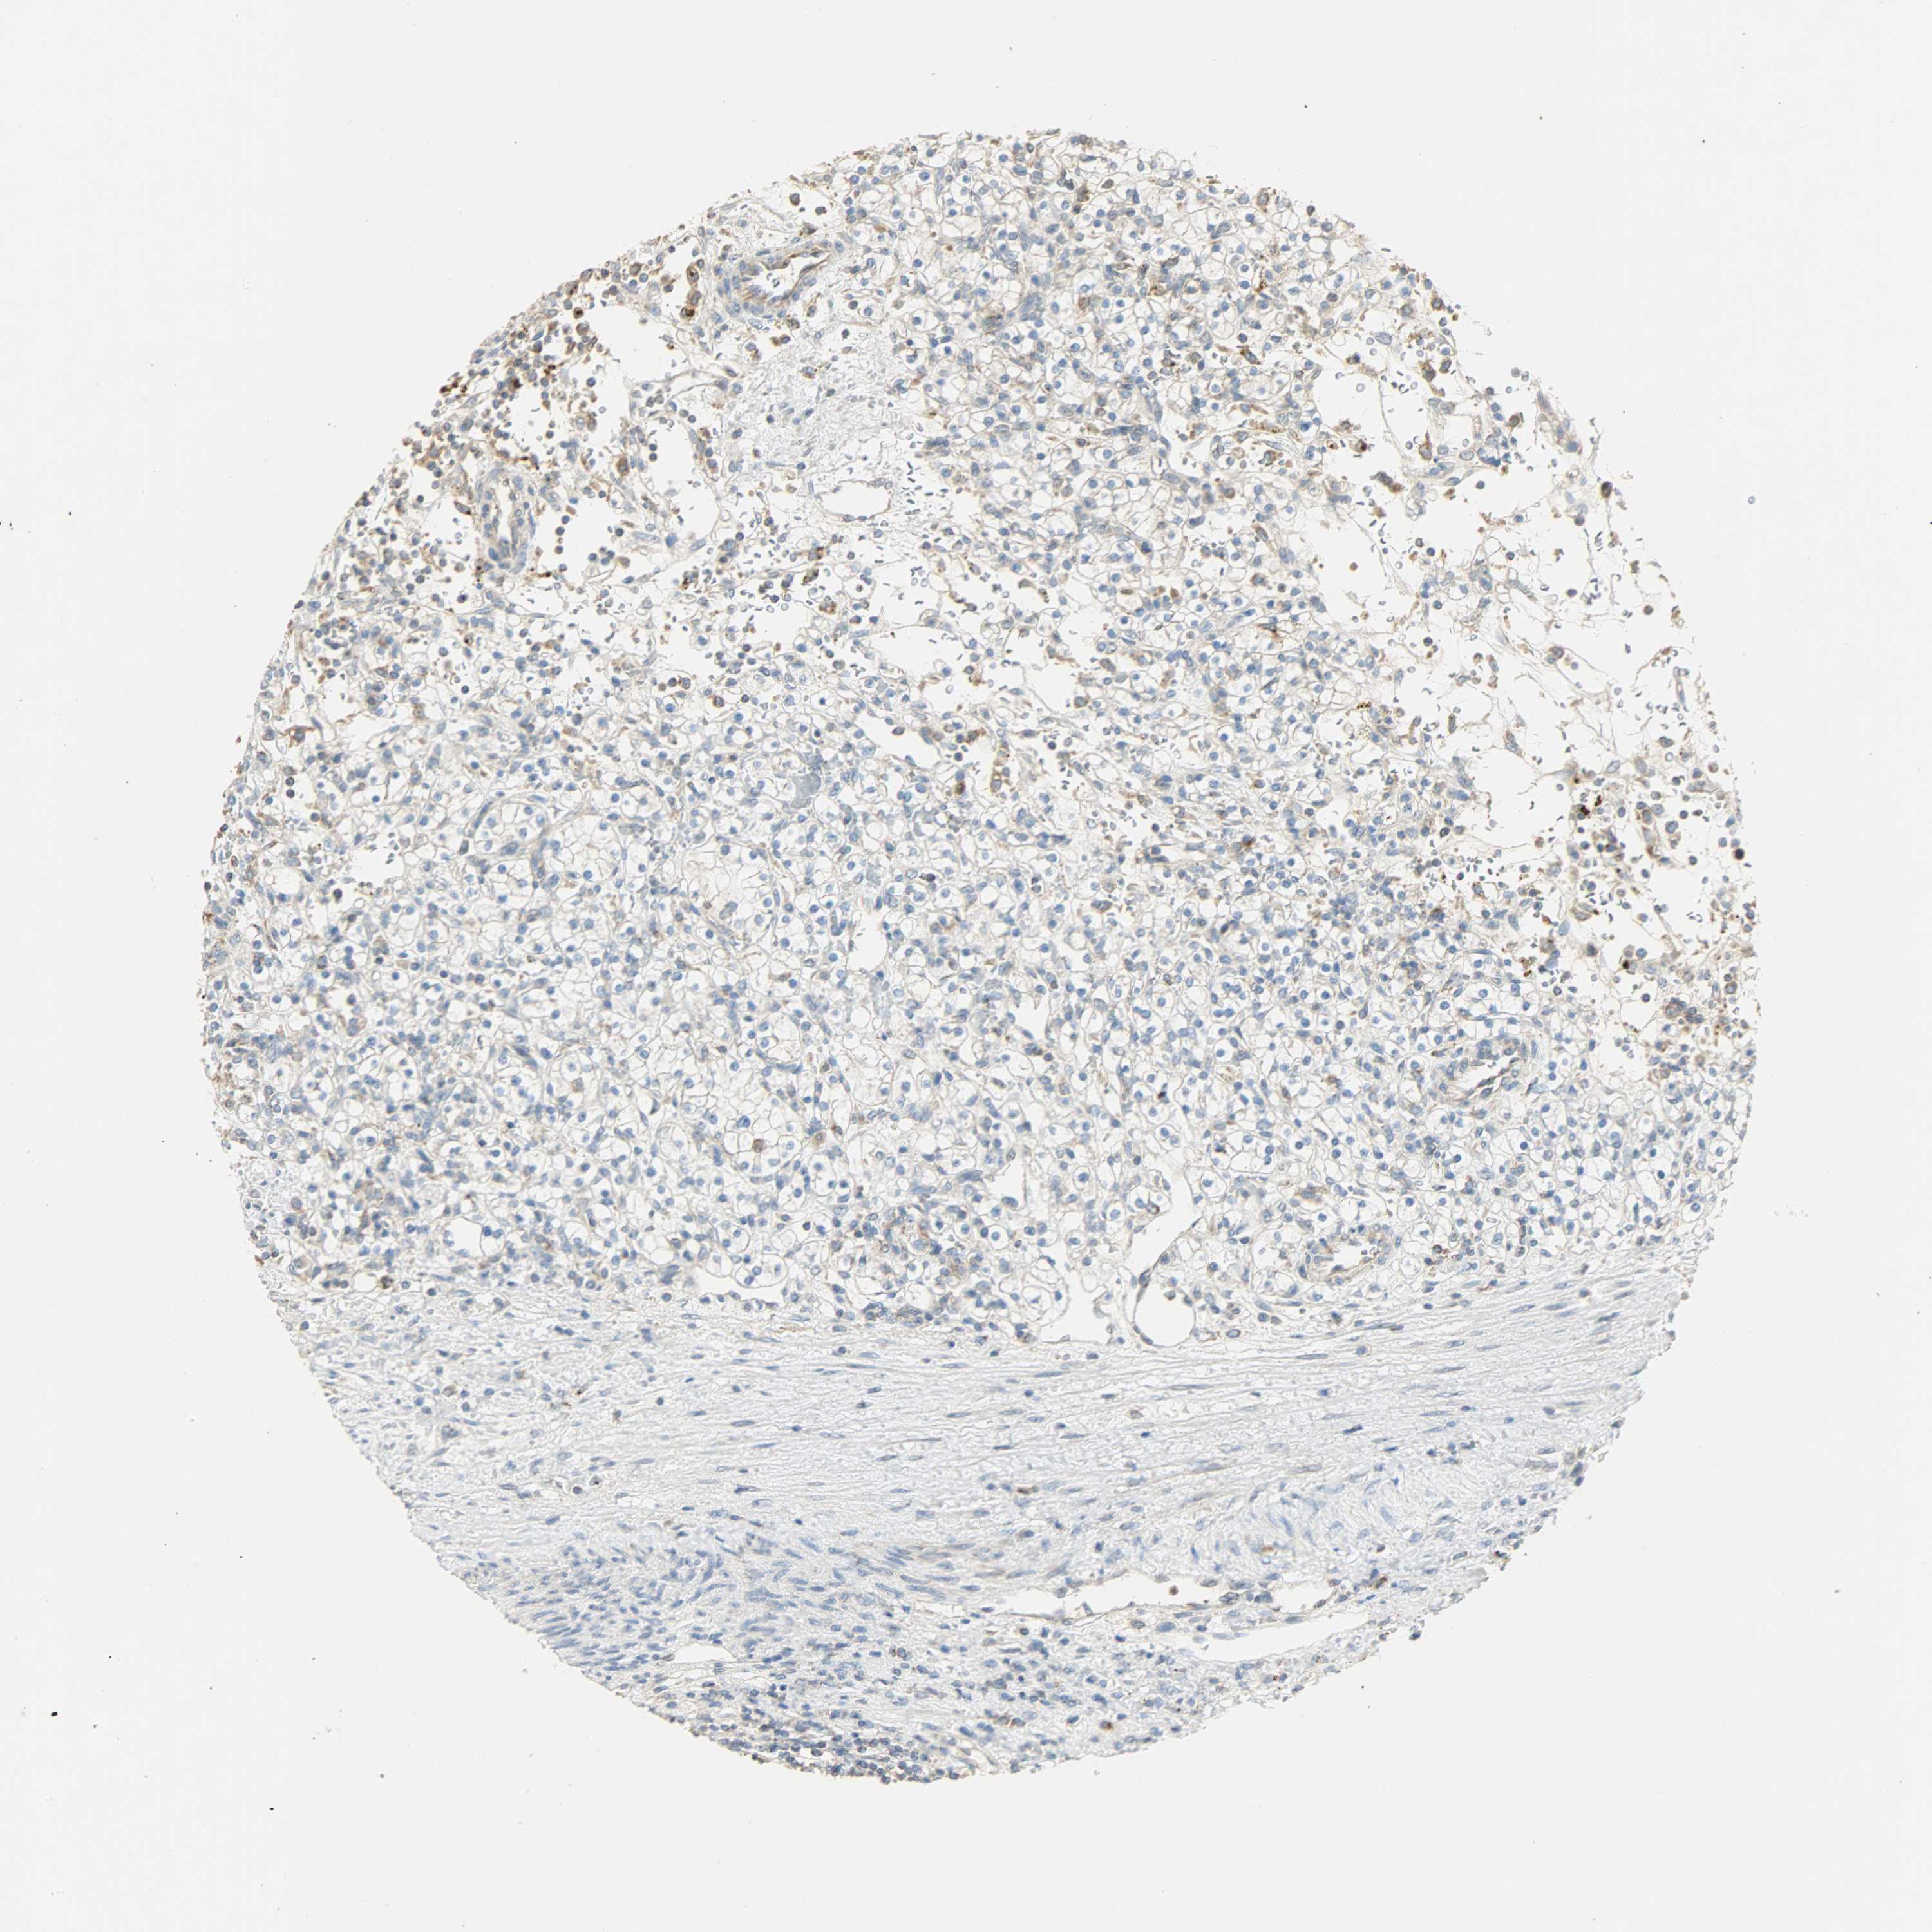

KIDNEY RENAL CLEAR CELL CARCINOMA (VALIDATION) - Interactive survival scatter ploti

The Survival Scatter plot shows the clinical status (i.e. dead or alive) for all individuals in the patient cohort, based on the same data that underlies the corresponding Kaplan-Meier plots. Patients that are alive at last time for follow-up are shown in blue and patients who have died during the study are shown in red.

The x-axis shows the expression levels (FPKM) of the investigated gene in the tumor tissue at the time of diagnosis. The y-axis shows the follow-up time after diagnosis (years). Both axes are complimented with kernel density curves demonstrating the data density over the axes. The top density plot shows the expression levels (FPKM) distribution among dead (red) and alive patients (blue). The right density plot shows the data density of the survived years of dead patients with high and low expression levels respectively, stratified using the cutoff indicated by the vertical dashed line through the Survival Scatter plot. This cutoff is automatically defined based on the FPKM cutoff that minimizes the p-score. The cutoff can be changed by dragging the vertical line or by entering a cutoff value in the square labeled "Current cut-off".

Under the Survival Scatter plot the p-score landscape (black curve; left axis) is shown together with dead median separation (red curve; right axis). Dead median separation is the difference in median mRNA expression between patients who have died with high and low expression, respectively. It is calculated as follows: median FPKM expression of dead patients with high expression - median FPKM expression of dead patients with low expression. This is intended to aid the user in visually exploring custom cutoffs and the associated p-scores and dead median separation.

Individual patient data is displayed and can be filtered by clicking on one or more of the category buttons on the top of the page. Categories describing expression level and patient information include: high, low, alive, dead, female, male and tumor stages. The scale of the x-axis can be toggled between linear and log-scale by clicking on the "x log" button. Mouse-over function shows TCGA ID, patient information and mRNA expression (FPKM) for each patient.

& Survival analysisi

Kaplan-Meier plots summarize results from analysis of correlation between mRNA expression level and patient survival. Patients were divided based on level of expression into one of the two groups "low" (under cut off) or "high" (over cut off). X-axis shows time for survival (years) and y-axis shows the probability of survival, where 1.0 corresponds to 100 percent.

NNT is not prognostic in Kidney Renal Clear Cell Carcinoma (validation)

Best expression cut offi

Based on the FPKM value of each gene, patients were classified into two groups and association between prognosis (survival) and gene expression (FPKM) was examined. The best expression cut-off refers the FPKM value that yields maximal difference with regard to survival between the two groups at the lowest log-rank P-value. Best expression cut-off was selected based on survival analysis .

When clicking on this number, the vertical dashed line indicating cut-off, the interactive survival plot, and the Kaplan-Meier curve will be adjusted to show results based on the best expression cut-off.

: 19.26

TCGA RNA samplesi

RNA-seq data is reported as average FPKM (number Fragments Per Kilobase of exon per Million reads), generated by the The Cancer Genome Atlas (TCGA) .

Normal distribution across the dataset is visualized with box plots, shown as median and 25th and 75th percentiles. Points are displayed as outliers if they are above or below 1.5 times the interquartile range. FPKM values of the individual samples are presented next to the box plot.

Average pTPM 30.0

Number of samples 100